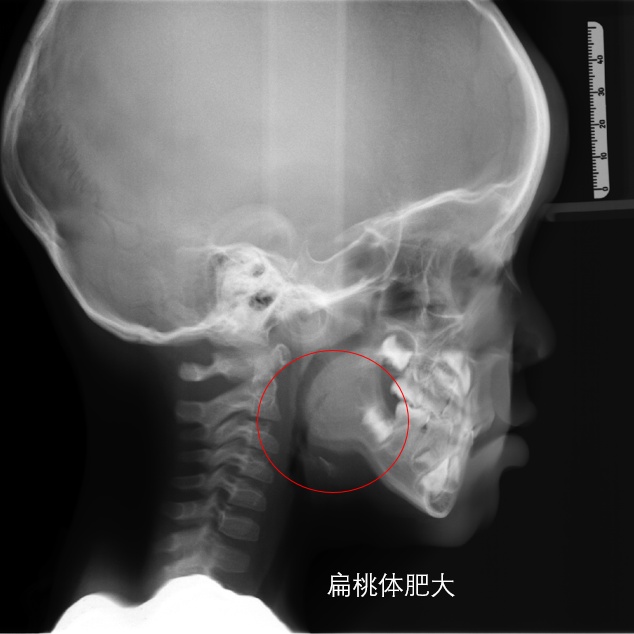

四、扁桃体肥大:扁桃体肥大造成宝宝通气不畅时,容易出现下颌前伸的姿势保证呼吸通畅,久而久之,易造成地包天;

2. 宝宝经常头前倾、呼吸不通畅的宝妈们注意啦!建议及时至耳鼻喉科会诊扁桃体肥大,早期切除过度肥大的扁桃体,使儿童呼吸道保持通畅,还原健康生长姿势。